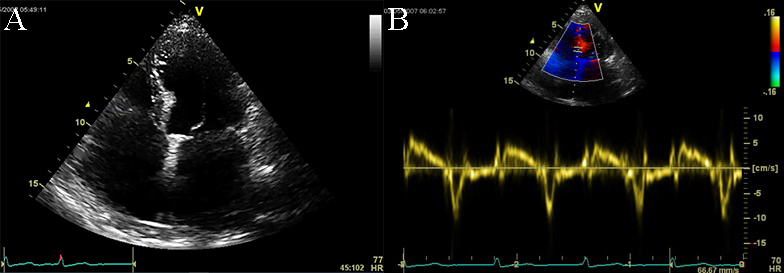

Fig. 10.Echocardiographic aspect of RCM. (A) Apical 4c view of an

elderly patient with idiopathic restrictive cardiomyopathy, severe biatrial

enlargement (left atrium

Doppler echocardiography and tissue Doppler imaging show diastolic dysfunction, frequently with a restrictive pattern. Different aspects of the diastolic function can be revealed, but usually more than grade 2 diastolic dysfunction, with increased filling pressures: an elevated peak mitral inflow velocity (high velocity of E wave), rapid early mitral inflow deceleration (low deceleration time). E/A ratio greater than 0.8, deceleration time of E wave lower than 200 milliseconds, and frequently lower than 160 milliseconds, E/e’ ratio with a value above 9, are features found in the echocardiographic examination of RCM (see Fig. 10 and Appendix Video 5) [1, 4].